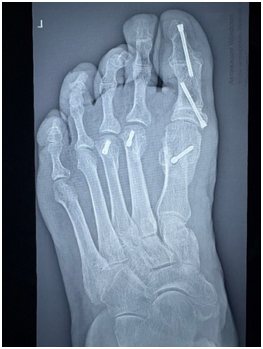

В ноябре 2024 года выполнена операция – реконструкция переднего отдела стопы в объеме: корригирующая медиализирующая остеотомия I плюсневой кости, фиксация винтом; корригирующая открытоугольная остеотомия основной фаланги I пальца с костной пластикой, фиксация винтом; корригирующий артродез межфалангового сустава I пальца, фиксация винтом; корригирующая остеотомия II-III плюсневой кости, фиксация винтом; корригирующий артродез дистального межфалангового сустава IV пальца, фиксация спицей (рис.3, рис.4).

Рис. 4. Рентгенограмма левой стопы после операции (прямая проекция)

Fig. 4. Radiograph of the left foot after surgery (AP radiograph)

Согласно действующему в клинике протоколу послеоперационного ведения пациентов с аналогичными хирургическими вмешательствами, был реализован комплекс мер, включающий 6-недельную иммобилизацию оперированной стопы в ортопедическом ботинке, обеспечивающего разгрузку переднего отдела. В ходе стационарного лечения проводился динамический мониторинг клинического статуса пациентки и ключевых клинико-лабораторных параметров, в результате которого не было выявлено каких-либо отклонений от референтных значений, что позволило перевести пациентку на амбулаторный этап ведения. На 14-ые сутки после операции выполнено снятие швов. Последующая контрольная рентгенография через 6 недель не выявила патологических изменений, иммобилизация послеоперационной обувью была прекращена и рекомендовано поэтапное увеличение двигательной активности с контролируемой осевой нагрузкой. В рамках комплексной реабилитации были предписаны курсовые физиопроцедуры и сеансы лимфодренажного массажа. В результате проведённых мероприятий удалось добиться полного купирования послеоперационного отёка и восстановления функциональной опороспособности стопы, что обеспечило возможность возвращения пациентки к привычному ритму двигательной активности без каких-либо ограничений (рис. 5, рис. 6).